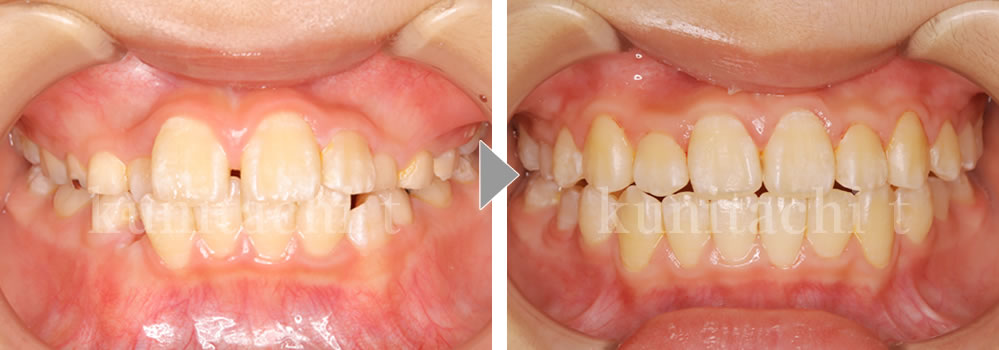

小児矯正治療前後の比較

これから小臼歯が生えそろい、しっかり噛めるようになっていきます。でも、低位舌があると歯並びに影響が出ることも…。「上顎に舌!唇をとじる!鼻呼吸!」良い歯並びをつくるおまじないです。

第2大臼歯も萌出して永久歯列が良い状態で完成しました。